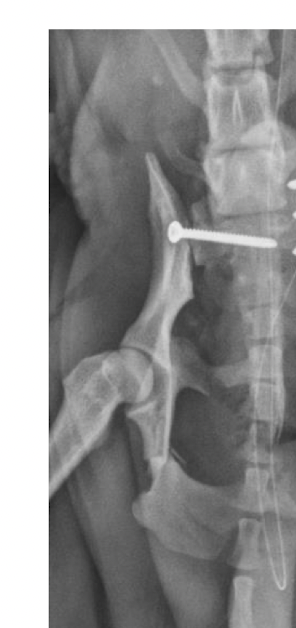

if there is a pelvic fracture then

A

there is usually at least 3 fractures

ilial fracture

sarcoiliac (SI) luxation

articular (acetabular)

3 criteria for fixation of pelvic fracture

on weight bearing axis

Ilial fractures

Sacroiliac (SI) luxations

how to fix pelvic fracture

bone plating

used for ilial and acetabular fractures

can use lag screws for SI luxation

how to fix SI luxation

lag screw